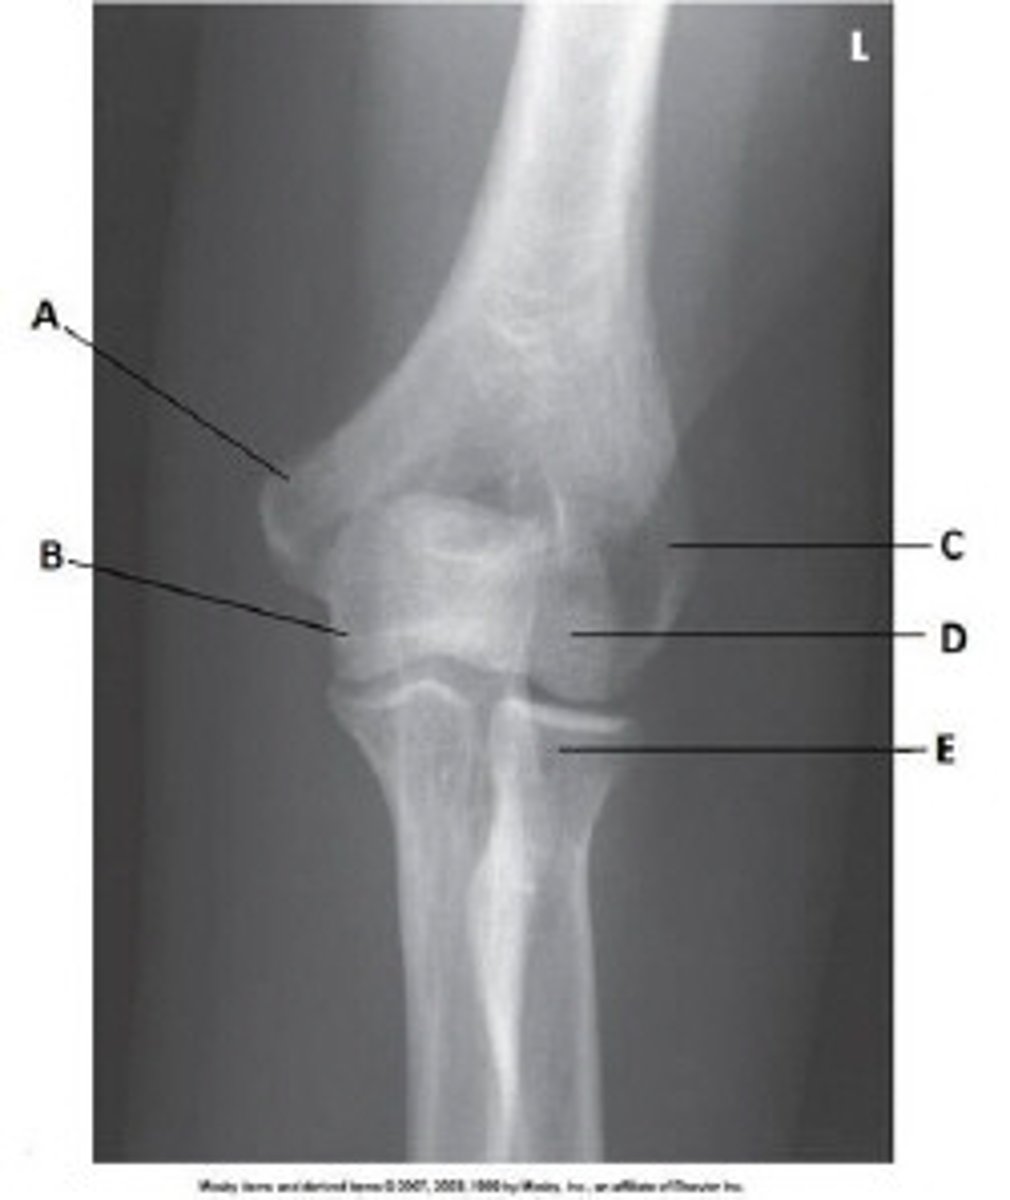

Capitulum

Coronoid process of ulna

What anatomy is labeled with the letter B in the image below?

Proximal tibiofibular joint

Lateral femoral condyle